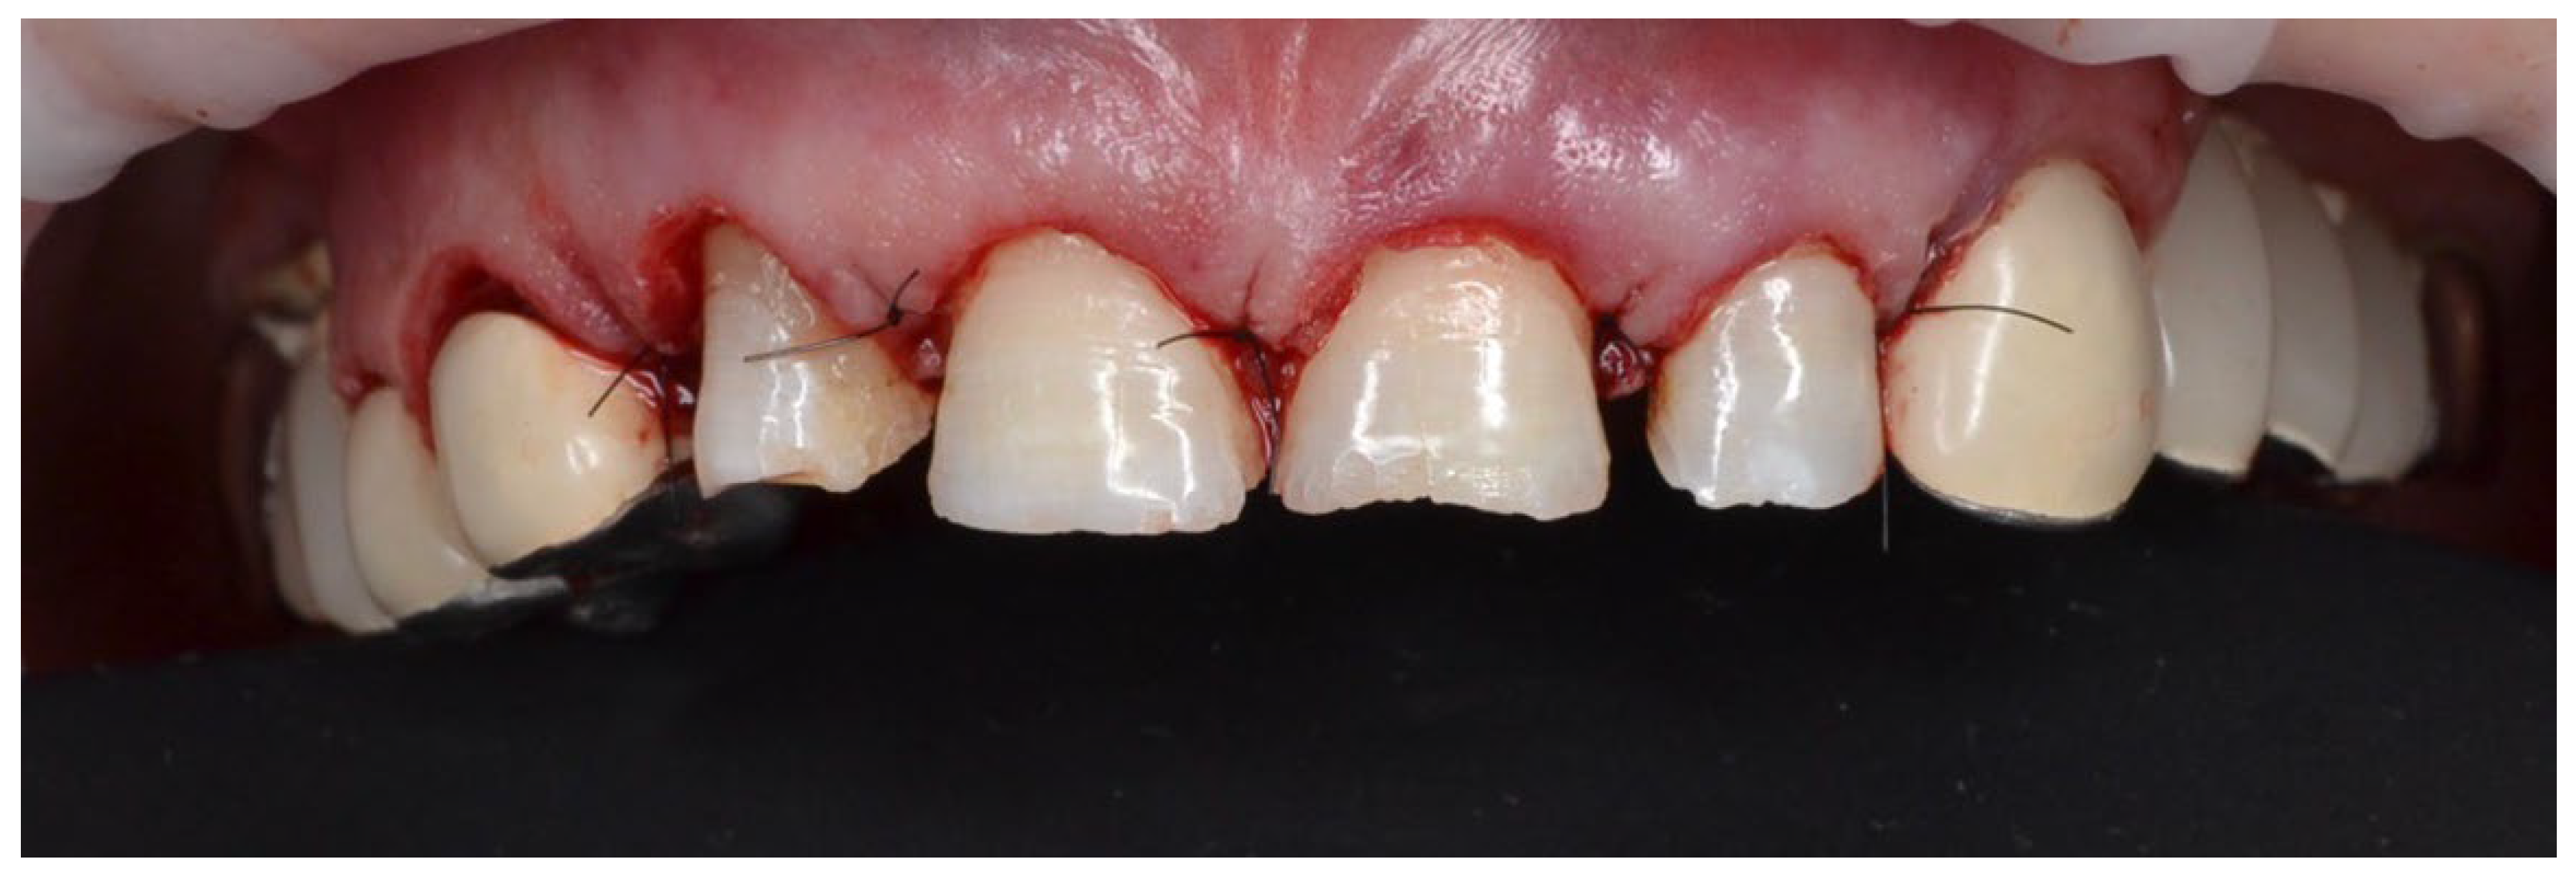

4.1. Case 1

4.2. Case 2